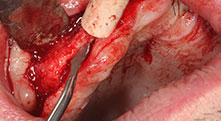

Piezomed B6

La cresta alveolar se ranura en ambos lados mediante piezocirugía (inserto: Piezomed B6). La implantación se realiza en la misma intervención y el hueso que rodea el implante se estructura además con una regeneración ósea guiada (GBR).